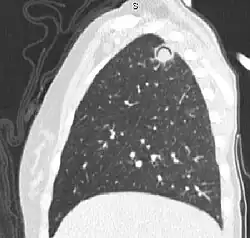

| The arrows denote an ill-defined nodular opacity in medial aspect of right upper lobe with ill-defined rim of lucency surrounding it | |

In radiology, the air crescent sign (also called the Monad sign[1]) is a finding on chest radiograph and computed tomography that is crescenteric and radiolucent, due to a lung cavity that is filled with air and has a round radiopaque mass.[2] Classically, it is due to an aspergilloma, a form of aspergillosis, that occurs when the fungus Aspergillus grows in a cavity in the lung.[3]